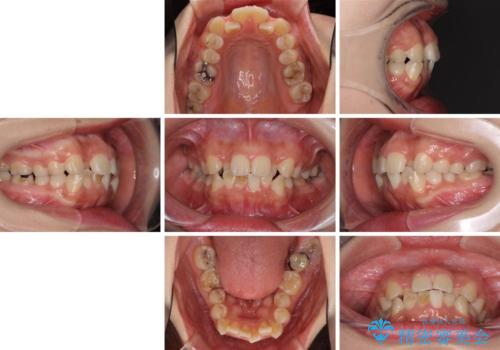

デコボコと膨らんだ口元 ハーフリンガルによる抜歯矯正とインプラント補綴治療

- 前歯のデコボコと上顎の前突感による口の閉じにくさを気にして来院された患者様です。

目立たない装置を希望されたので、上顎が裏側装置のハーフリンガルを選択し、上下左右の小臼歯(計4歯)を抜歯して矯正治療を行うこととしました。

また、左下の奥歯は抜歯が必要な歯であったため、矯正治療中の良いタイミングで抜歯とインプラント埋入を行い、矯正治療後にオールセラミッククラウンで補綴治療を行うこととしました。

デコボコの解消までは非常にスムーズでしたが、咬合力が強いためか、スペースを閉じるまでに長い期間を要しました。